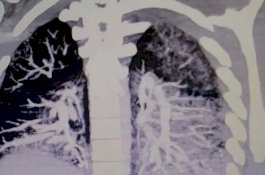

X-ray Tunjukkan Paru-paru Pengguna E-Rokok Dilapisi Minyak Mengeras

Health